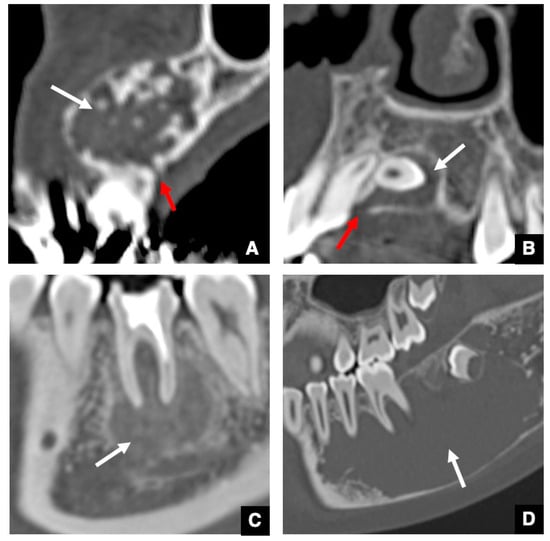

3. Relationship between GT and Odontomas

4. Significance of GTs for Differential Diagnosis between Odontogenic and Non-Odontogenic Masses